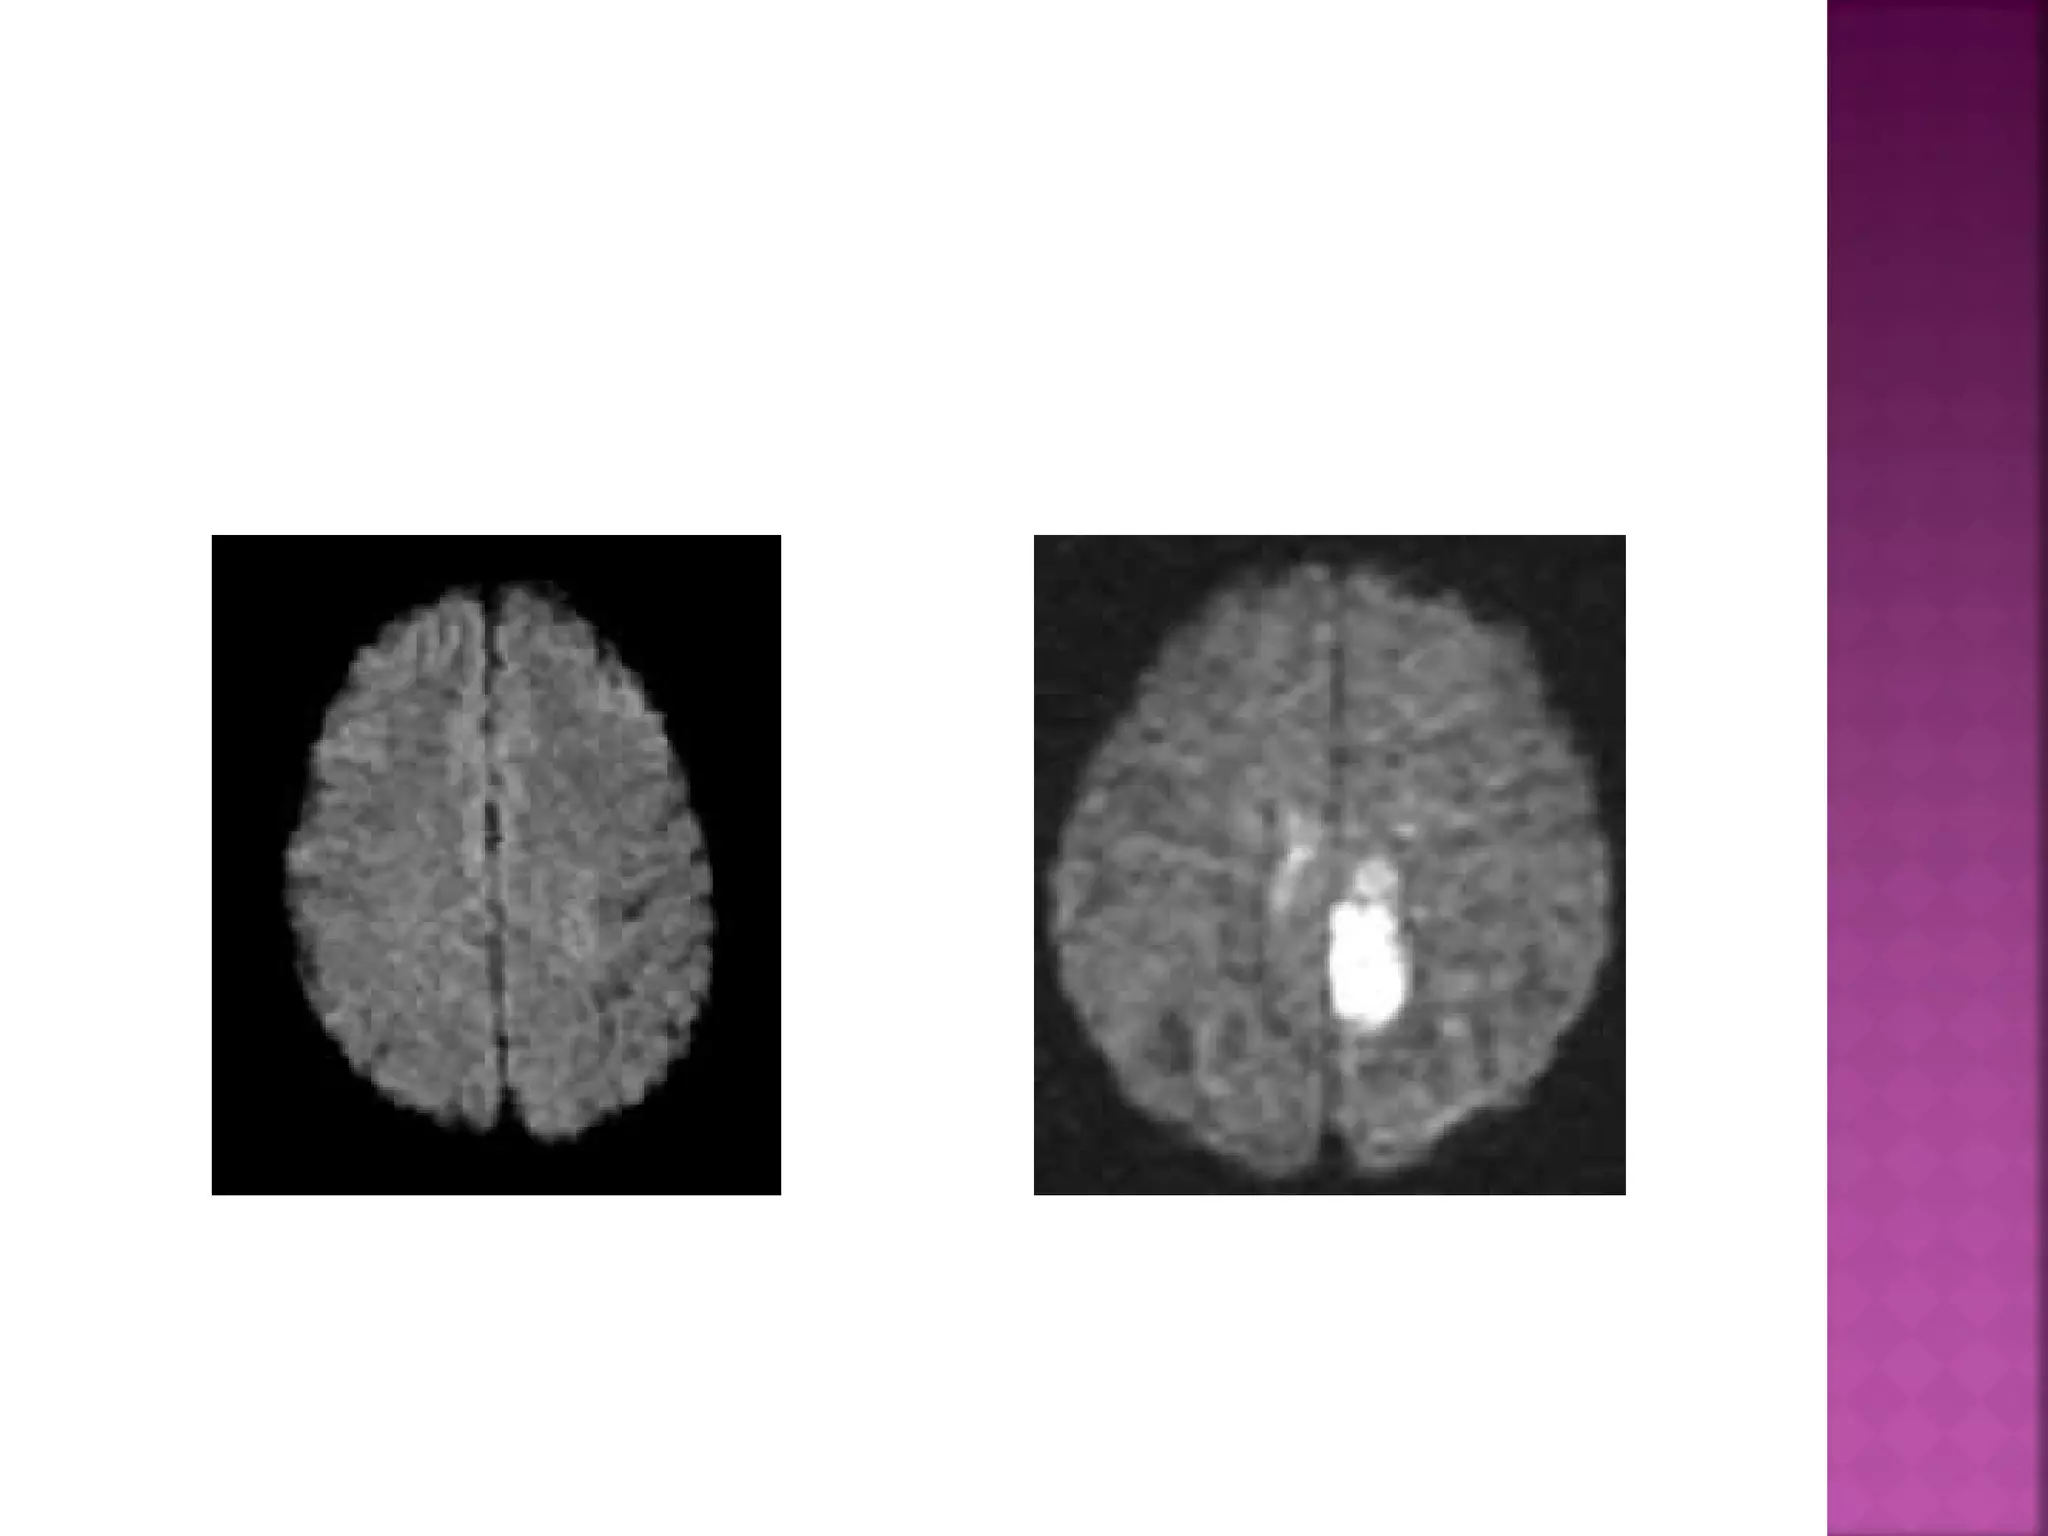

DWI is the most sensitive sequence for stroke

imaging.

DWI is sensitive to restriction of Brownian

motion of extracellular water due to

imbalance caused by cytotoxic edema.

Normally water protons have the ability to

diffuse extracellularly and loose signal.

High intensity on DWI indicates restriction of

the ability of water protons to diffuse

extracellularly.

DWI is already positive in the acute phase

and then becomes more bright with a

maximum at 7 days.

DWI in brain infarction will be positive for

approximately for 3 weeks after onset (in

spinal cord infarction DWI is only positive for

one week!).

 DWI is themost sensitive sequence for stroke imaging. DWI is sensitive to restriction of Brownian motion of extracellular water due to imbalance caused by cytotoxic edema. Normally water protons have the ability to diffuse extracellularly and loose signal. High intensity on DWI indicates restriction of the ability of water protons to diffuse extracellularly.

  DWI is alreadypositive in the acute phase and then becomes more bright with a maximum at 7 days. DWI in brain infarction will be positive for approximately for 3 weeks after onset (in spinal cord infarction DWI is only positive for one week!).